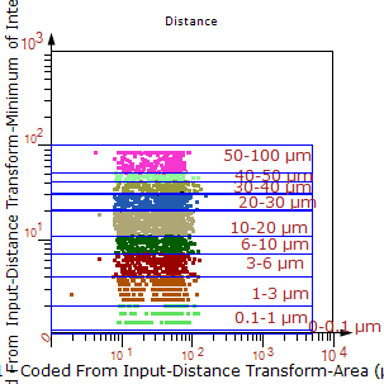

1. 利用TissueFAXS系统进行玻片荧光的全景扫描。

2. 使用StrataQuest分析软件进行定量分析。

6. 计算神经元与血管间的空间距离,并统计数量和占比。

血管与小胶质细胞的距离0-0.1μm(红色框线标记)

血管与小胶质细胞的距离0.1-1μm(粉色标记)

血管与小胶质细胞的距离1-3μm(粉色标记)

此外,Tissue Cytometry散点图-热力图-数据同屏叠加对比功能,可以整合多种数据分析的二维图像,便于研究者们直观的对比与校验;同时结合图像同屏对比功能,不但可以同屏预览,还可以支持多点实时联动缩放,便于观察/分析图像,打通信息分析时数据-图像之间的屏障。